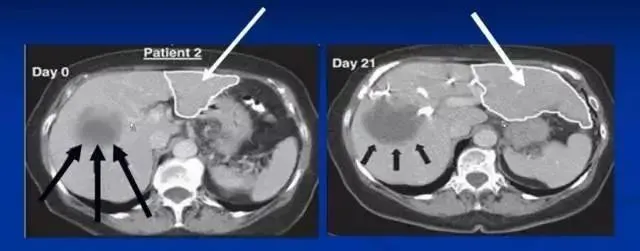

沈陽(yáng)軍區(qū)總醫(yī)院消化內(nèi)科郭曉鐘等經(jīng)股動(dòng)脈肝內(nèi)自體骨髓干細(xì)胞移植治療肝硬化102例報(bào)告。